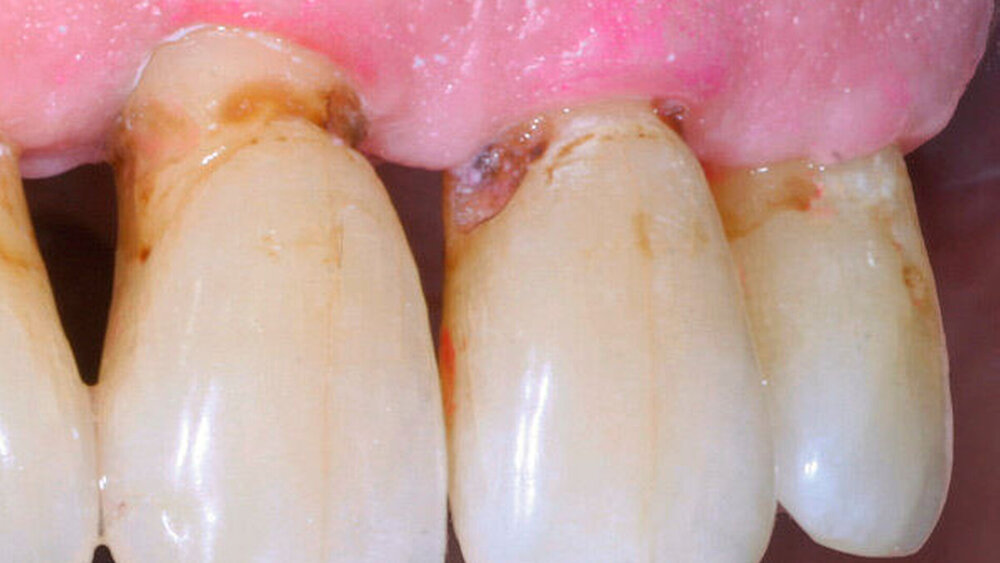

Durch Fortschritte in der zahnärztlichen Prävention und Therapie können Senioren heute ihre eigenen Zähne bis in ein hohes Alter behalten. Aufgrund altersbedingter Veränderungen – wie zum Beispiel der Rückbildung des Zahnhalteapparats – besteht für die erhaltenen Zähne jedoch ein hohes Risiko für die Entwicklung von Wurzelkaries (Abbildung 1).

In der aktuellen Deutschen Mundgesundheitsstudie (DMS V) konnte gezeigt werden, dass insbesondere Zähne von pflegebedürftigen Senioren häufig Wurzelkaries aufweisen. Da Wurzelkariesläsionen in unzugänglichen Bereichen wie Approximalräumen schwer zu therapieren sind (Abbildung 2) und die Therapieoptionen bei pflegebedürftigen Patienten meist eingeschränkt sind, ist es von großer Bedeutung, der Entstehung von Wurzelkaries bei Senioren vorzubeugen.